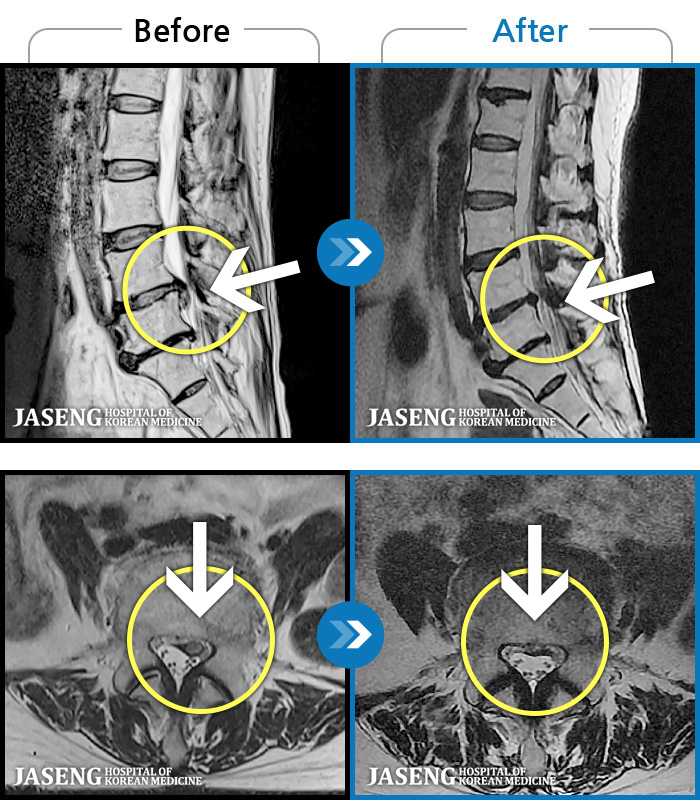

[ؿ] 23.09.18~25.01.27

ȯںп Ǹ ǿ ԿǾ, ο ġ ۿ Ƿ ġḦ Ͻñ ٶϴ.